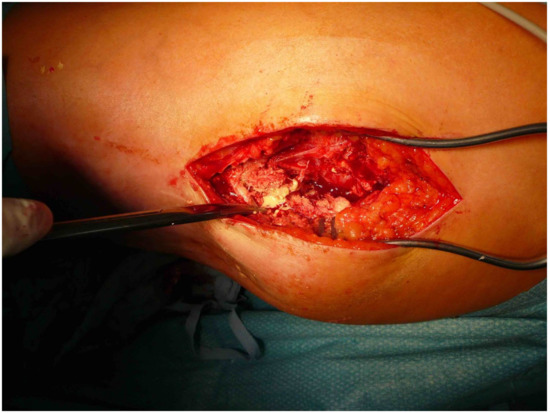

The patients presented with calcifications in the large muscle groups (gluteal, quadriceps, and gastrocnemius muscles). These spread to tendons and subcutaneous tissue (Figure 2). Four patients had previously undergone trial biopsies, and three of these four subsequently developed a fistula with secondary bacterial colonization of the wound. Surgical therapy was based on the extent of the lesions and consisted of the most radical exstirpation of the affected tissue. In these cases, solid tumor-like calcifications were usually found adjacent to pasty changes (Figure 3).

Figure 3. Intraoperative situs of a tumoral calcinosis with solid and liquid portions. ©Dr. I. Tarner, Bad Nauheim.